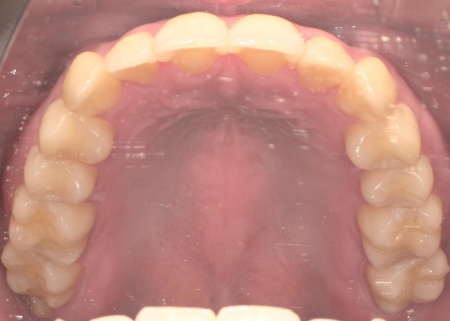

20代女性 八重歯と歯並びの乱れをマウスピース矯正装置で改善した症例

拝見したところ、歯が正しく並ぶためのスペースが不足しており、歯が重なって生えてしまう叢生(そうせい)の状態が全体的に見られました。

矯正治療終了後、歯並びの後戻りを防ぐための保定装置を装着していただきました。

経過観察を行い問題がないことを確認して、治療を終了しました。